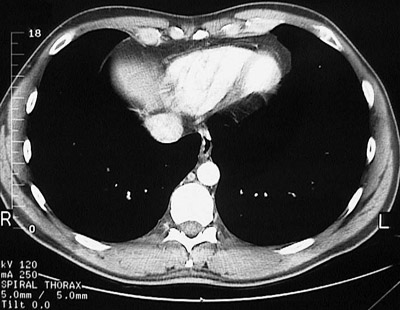

[T10] This is a normal chest CT scan demonstrating the right lung and left lung and liver and inferior vena cava and right ventricle and interventricular septum and left ventricle and xyphoid process and descending aorta and azygous vein and esophagus and serratus anterior muscle and latissimus dorsi muscle and trapezius muscle and sacrospinalis muscle and transversospinal muscle in the upper chest.